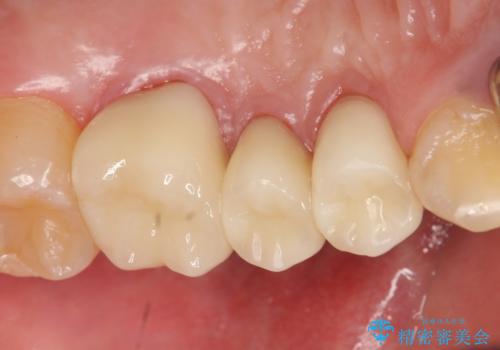

- 左上奥歯の銀歯をセラミックにしたいといらっしゃった方の症例です。

銀歯を除去したところ歯茎よりも深い位置まで虫歯があったため、歯冠長延長術(歯周外科)を行いました。

その後歯茎の回復を待つ間に再根管治療を行い、歯茎の回復後オールセラミッククラウンにて補綴を行いました。

今回用いたオールセラミッククラウンはジルコニアフレームという白い素材の上にセラミックを盛っているため、審美性が非常に高いのが特徴です。

また、ジルコニアは人工ダイヤモンドの材料にも使われているほど高い強度を持っており、そのためオールセラミッククラウンは審美性だけでなく、奥歯やブリッジの補綴も可能とするクラウンです。